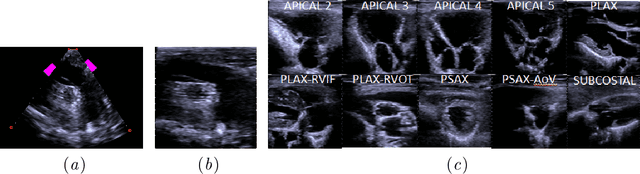

Abstract:Echocardiography provides an important tool for clinicians to observe the function of the heart in real time, at low cost, and without harmful radiation. Automated localization and classification of heart valves enables automatic extraction of quantities associated with heart mechanical function and related blood flow measurements. We propose a machine learning pipeline that uses deep neural networks for separate classification and localization steps. As the first step in the pipeline, we apply view classification to echocardiograms with ten unique anatomic views of the heart. In the second step, we apply deep learning-based object detection to both localize and identify the valves. Image segmentation based object detection in echocardiography has been shown in many earlier studies but, to the best of our knowledge, this is the first study that predicts the bounding boxes around the valves along with classification from 2D ultrasound images with the help of deep neural networks. Our object detection experiments applied to the Apical views suggest that it is possible to localize and identify multiple valves precisely.